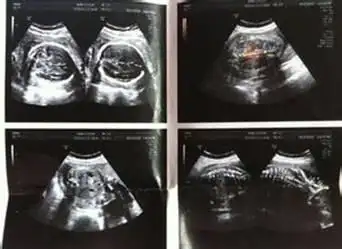

妇科b超,请选择最佳检查时间

专家谈产前b超检查的局限性不能筛查出所有畸形